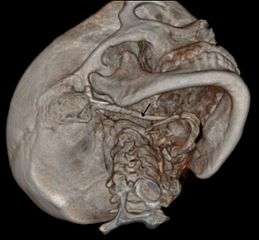

3D-reconstructed CT scan showing bilateral stylohyoid ligament ossification- 3D reconstructed CT scan showing elongated styloid process (right side)

Imaging is important and is diagnostic. Visualizing the styloid process on a CT scan with 3D reconstruction is the suggested imaging technique.[6] The enlarged styloid may be visible on an orthopantogram or a lateral soft tissue X ray of the neck.